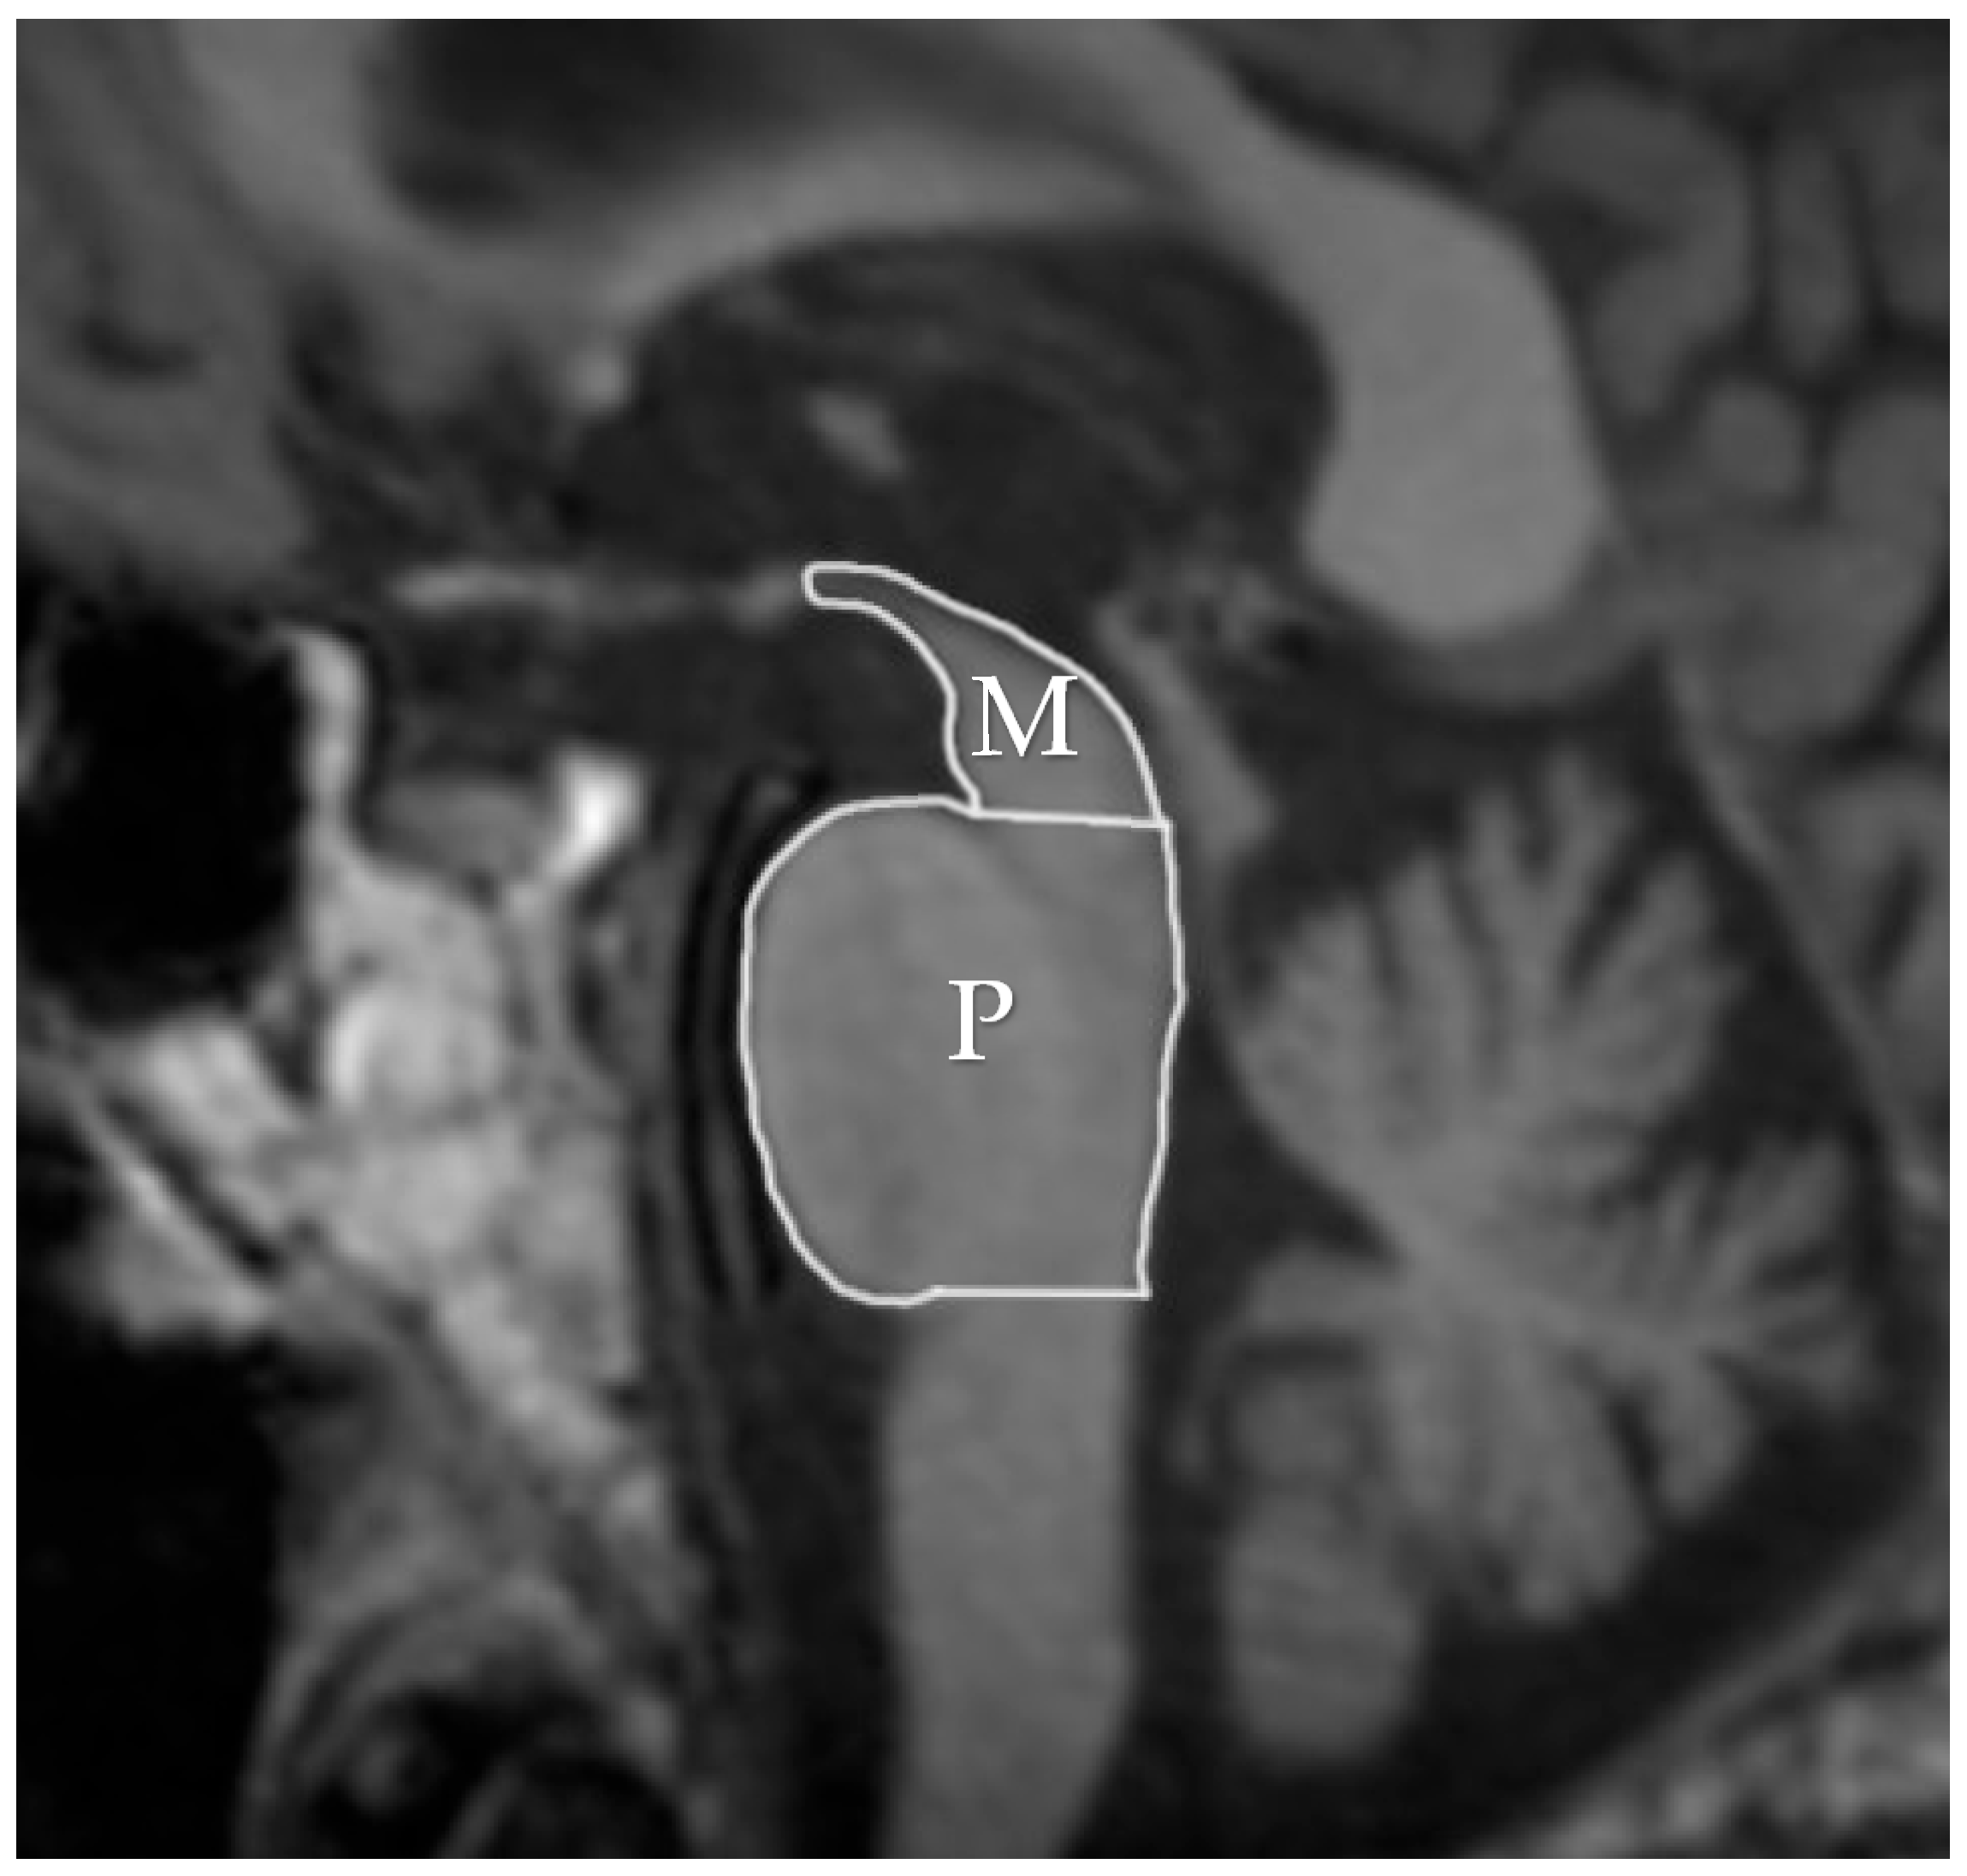

- Quattrone, A.; Morelli, M.; Williams, D.R.; Vescio, B.; Arabia, G.; Nigro, S.; Nicoletti, G.; Salsone, M.; Novellino, F.; Nisticò, R.; et al. MR parkinsonism index predicts vertical supranuclear gaze palsy in patients with PSP-parkinsonism. Neurology 2016, 87, 1266–1273. [Google Scholar] [CrossRef]

- Picillo, M.; Tepedino, M.F.; Abate, F.; Erro, R.; Ponticorvo, S.; Tartaglione, S.; Volpe, G.; Frosini, D.; Cecchi, P.; Cosottini, M.; et al. Midbrain MRI assessments in progressive supranuclear palsy subtypes. J. Neurol. Neurosurg. Psychiatry 2020, 91, 98–103. [Google Scholar] [CrossRef] [PubMed]

- Quattrone, A.; Morelli, M.; Nigro, S.; Quattrone, A.; Vescio, B.; Arabia, G.; Nicoletti, G.; Nisticò, R.; Salsone, M.; Novellino, F.; et al. A new MR imaging index for differentiation of progressive supranuclear palsy-parkinsonism from Parkinson’s disease. Parkinsonism Relat. Disord. 2018, 54, 3–8. [Google Scholar] [CrossRef]

- Madetko, N.; Alster, P.; Kutyłowski, M.; Migda, B.; Nieciecki, M.; Koziorowski, D.; Królicki, L. Is MRPI 2.0 More Useful than MRPI and M/P Ratio in Differential Diagnosis of PSP-P with Other Atypical Parkinsonisms? J. Clin. Med. 2022, 11, 2701. [Google Scholar] [CrossRef] [PubMed]